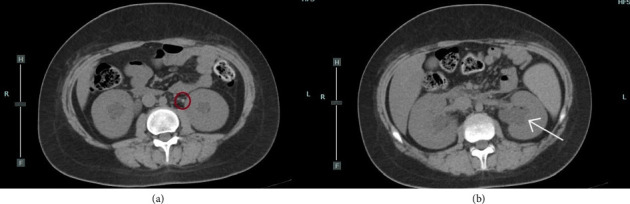

糖尿病酮症酸中毒(DKA)是儿童1型糖尿病(T1DM)的常见初始表现,发生率高达40%。DKA也可能与严重的并发症相关,包括肾结石。我们提出了一个12岁零8个月大的男孩谁发展急性肾损伤(AKI)继发于双侧尿路结石T1DM与DKA发病期间。在DKA的常规治疗后,实验室检查显示肌酐和氮血症升高。24小时后,患者出现腰痛和无尿。平片、超音波及电脑断层扫描显示双侧肾结石及盆腔扩张。我们进行了紧急双侧上升肾盂造影和支架置入。右侧输尿管支架置入成功,但左侧输尿管支架置入失败,原因是输尿管内解剖变异;因此,进行了肾造口术。利尿立即恢复,随后几天肾功能恢复正常,无永久性损害。据我们所知,这是第一例小儿DKA患者双侧结石合并输尿管狭窄的报道。对于严重DKA患者,我们建议在出现肌酐、少尿/无尿或腰痛异常升高时,采用低阈值的CT成像常规监测肾功能。早期多学科干预可迅速缓解肾后梗阻,预防永久性肾损害,改善预后。

Diabetic ketoacidosis (DKA) is a common initial presentation of type 1 diabetes mellitus (T1DM) in children occurring in up to 40% of cases. DKA can also be associated with severe complications, including nephrolithiasis. We present the case of a 12 years and 8-month-old boy who developed acute kidney injury (AKI) secondary to bilateral urinary lithiasis during the onset of T1DM with DKA. After conventional treatment for DKA, laboratory tests showed increased creatinine and azotemia. 24 hours later, he developed lumbar pain and anuria. Plain radiography, ultrasonography, and computed tomography (CT) revealed bilateral renal calculi and pelvic dilation. An urgent bilateral ascending pyelography with stent placement was performed. Right ureteral stenting was successful, but left stenting failed due to an intramural ureteral anatomical variant; thus, a nephrostomy was performed. Diuresis resumed immediately, and renal function normalized over the following days without permanent impairment. To our knowledge, this is the first reported case of bilateral lithiasis with ureteral stenosis in a pediatric patient with DKA. In patients with severe DKA, we recommend routine monitoring of kidney function with a low threshold for CT imaging whenever there is an unexpected rise in creatinine, oliguria/anuria, or lumbar pain. Early multidisciplinary intervention can promptly relieve postrenal obstruction, prevent permanent renal damage, and improve outcomes.